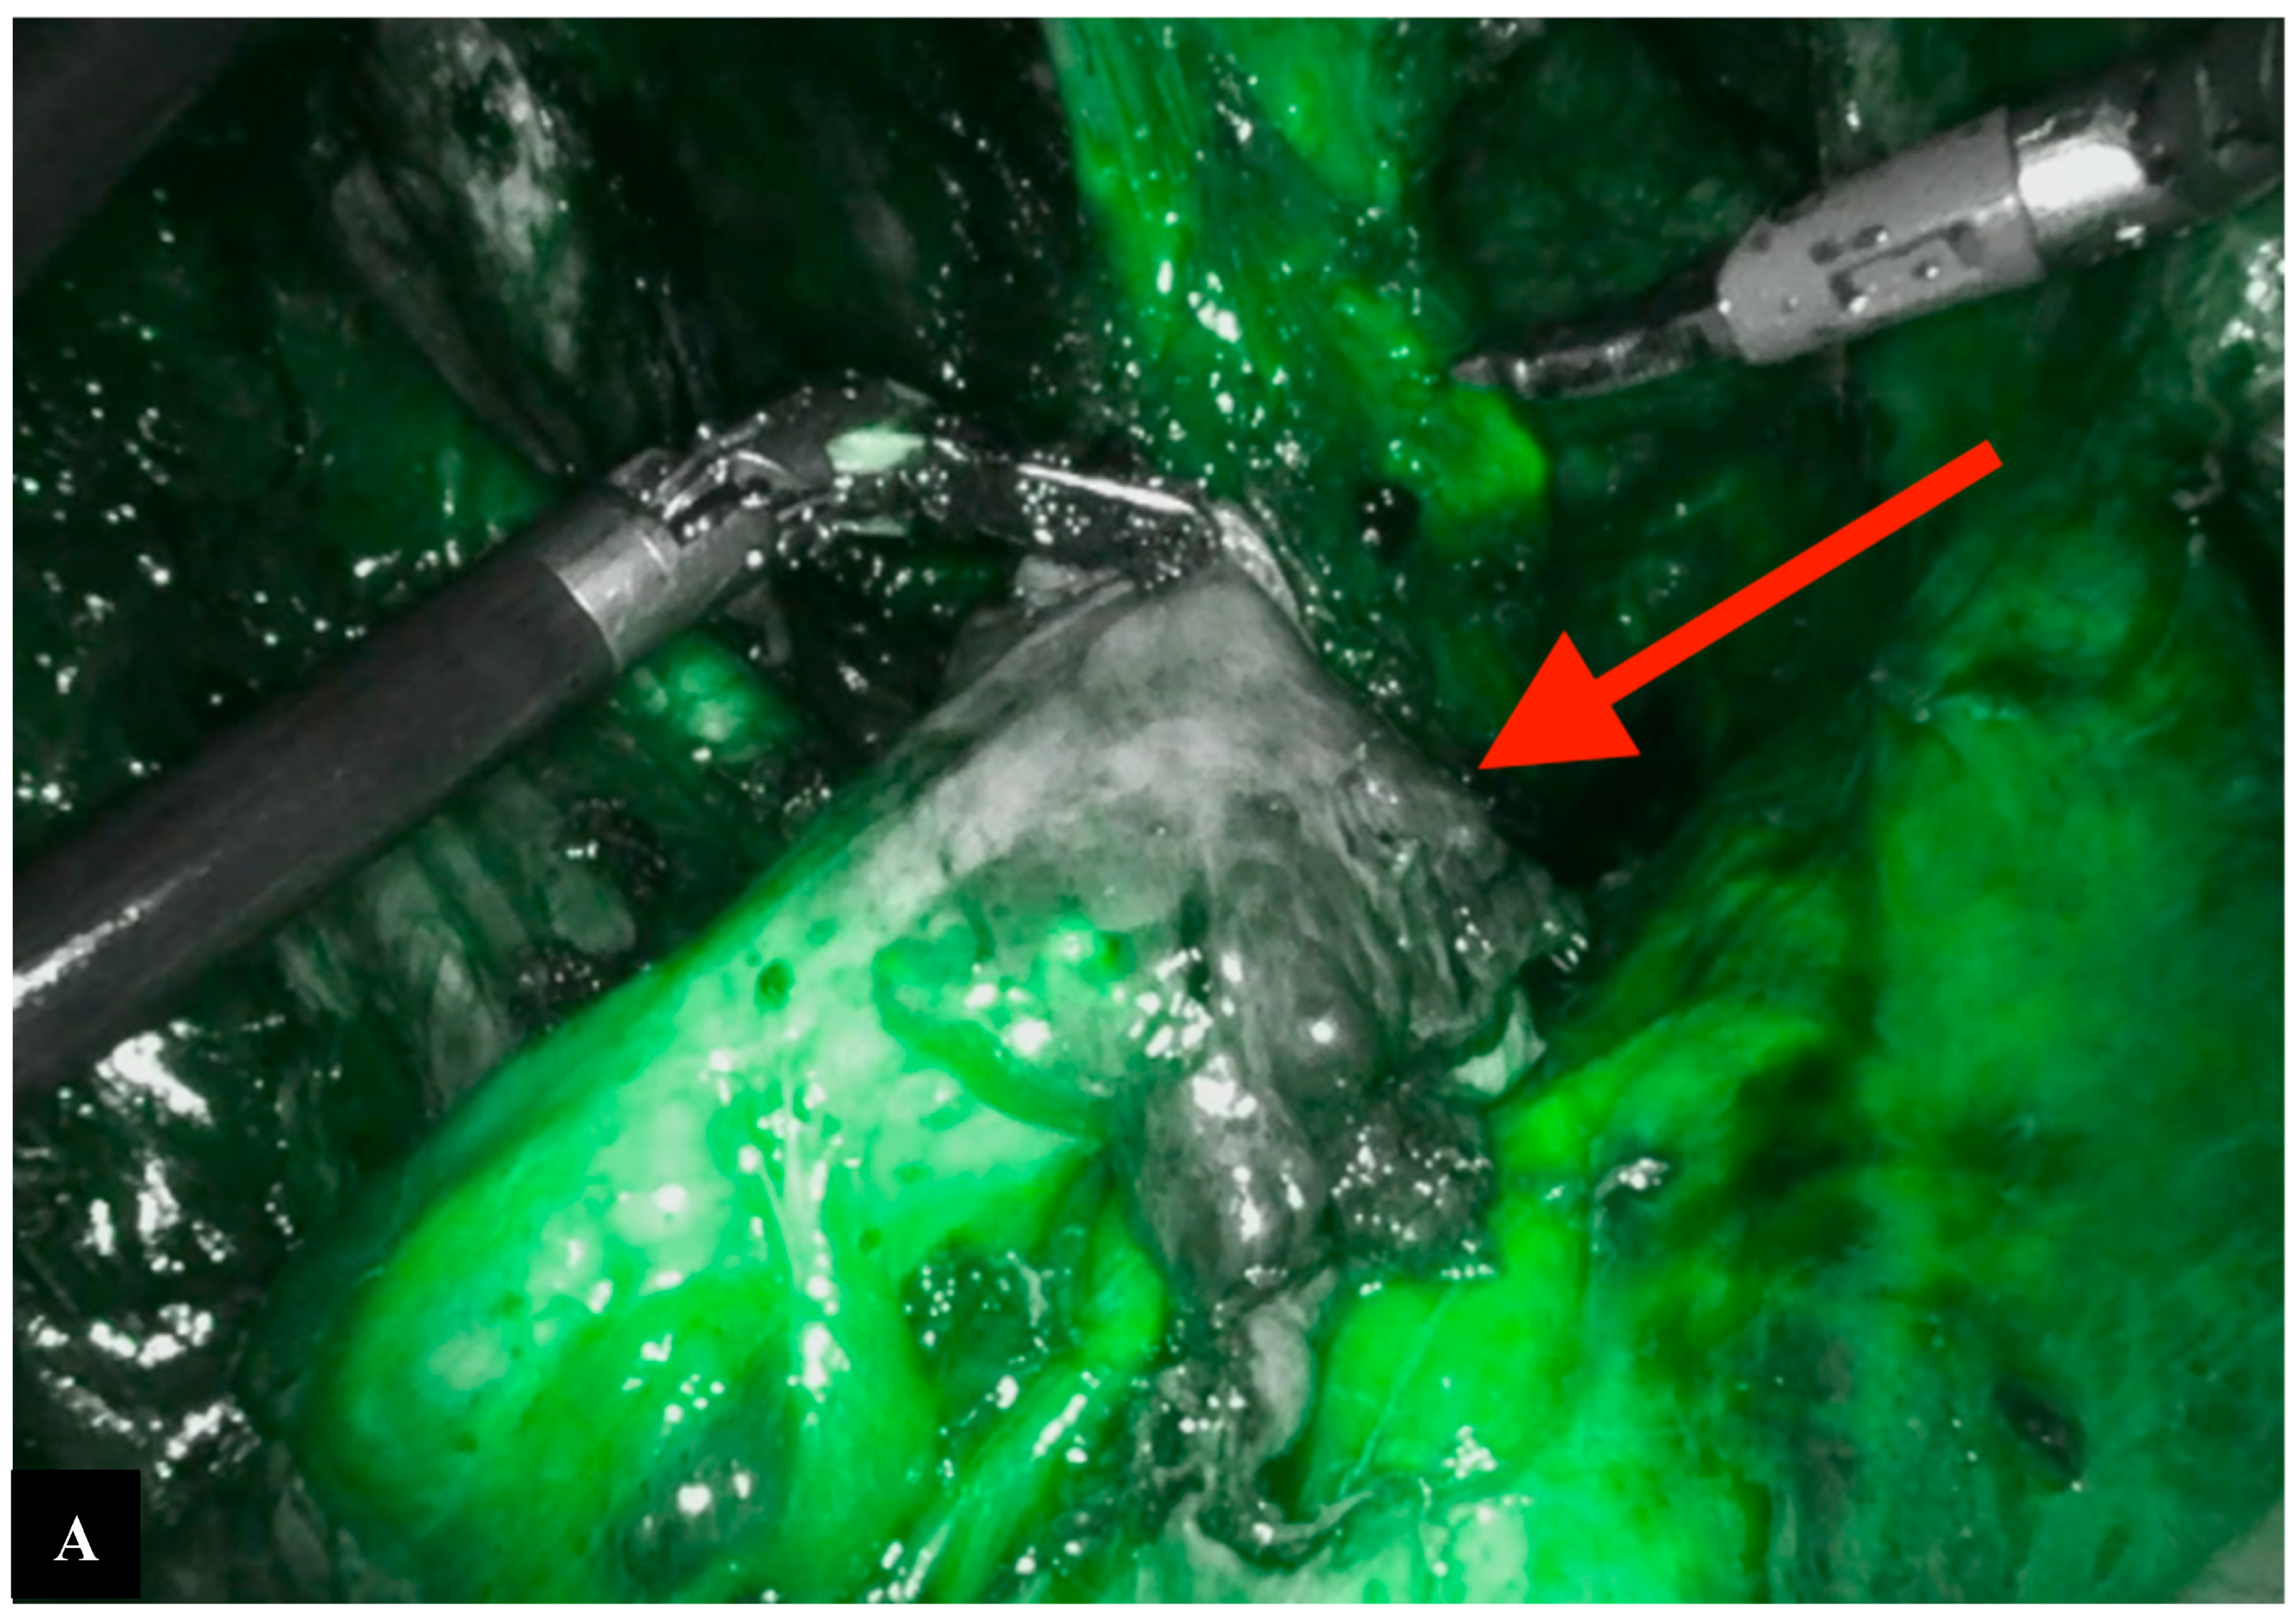

Operative Technique